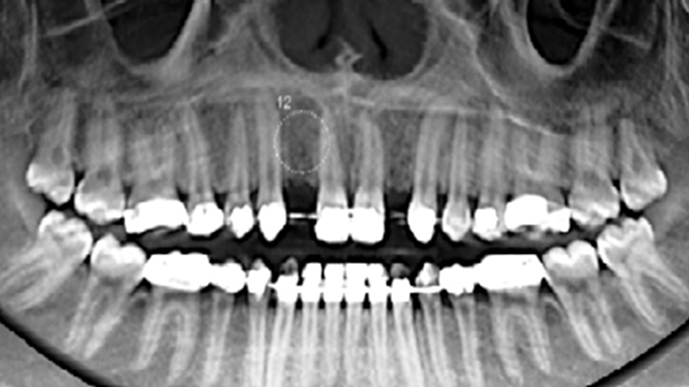

Socket Shield Technique, anterior esthetics, maxillary anterior, esthetic, esthetics, delayed implant placement, socket preservation, AnyRidge, Root Membrane Kit, Root Membrane Technique, Partial Extraction Therapy, PET, esthetic zone, fuse abutment, Dr. Yoshiharu Hayashi,#11,#21,#22

Anterior esthetics, MiNi, flap elevation, minimally invasive technique, soft tissue management, esthetic zone, Dr. Achraf Souayah, anterior aesthetics, aesthetic, aesthetics, esthetic, #12, #22